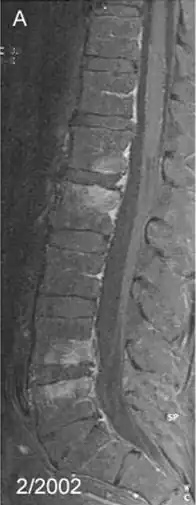

Спондилит — воспалительное заболевание позвоночника. Является одной из форм спондилопатии. При спондилите происходит первичное разрушение тел позвонков, что приводит к деформации позвоночника.

Спондилит может быть специфическим, например туберкулез позвоночника, сифилитический, гонорейный и др., а также неспецифический: гематогенный гнойный спондилит, а также болезнь Бехтерева.